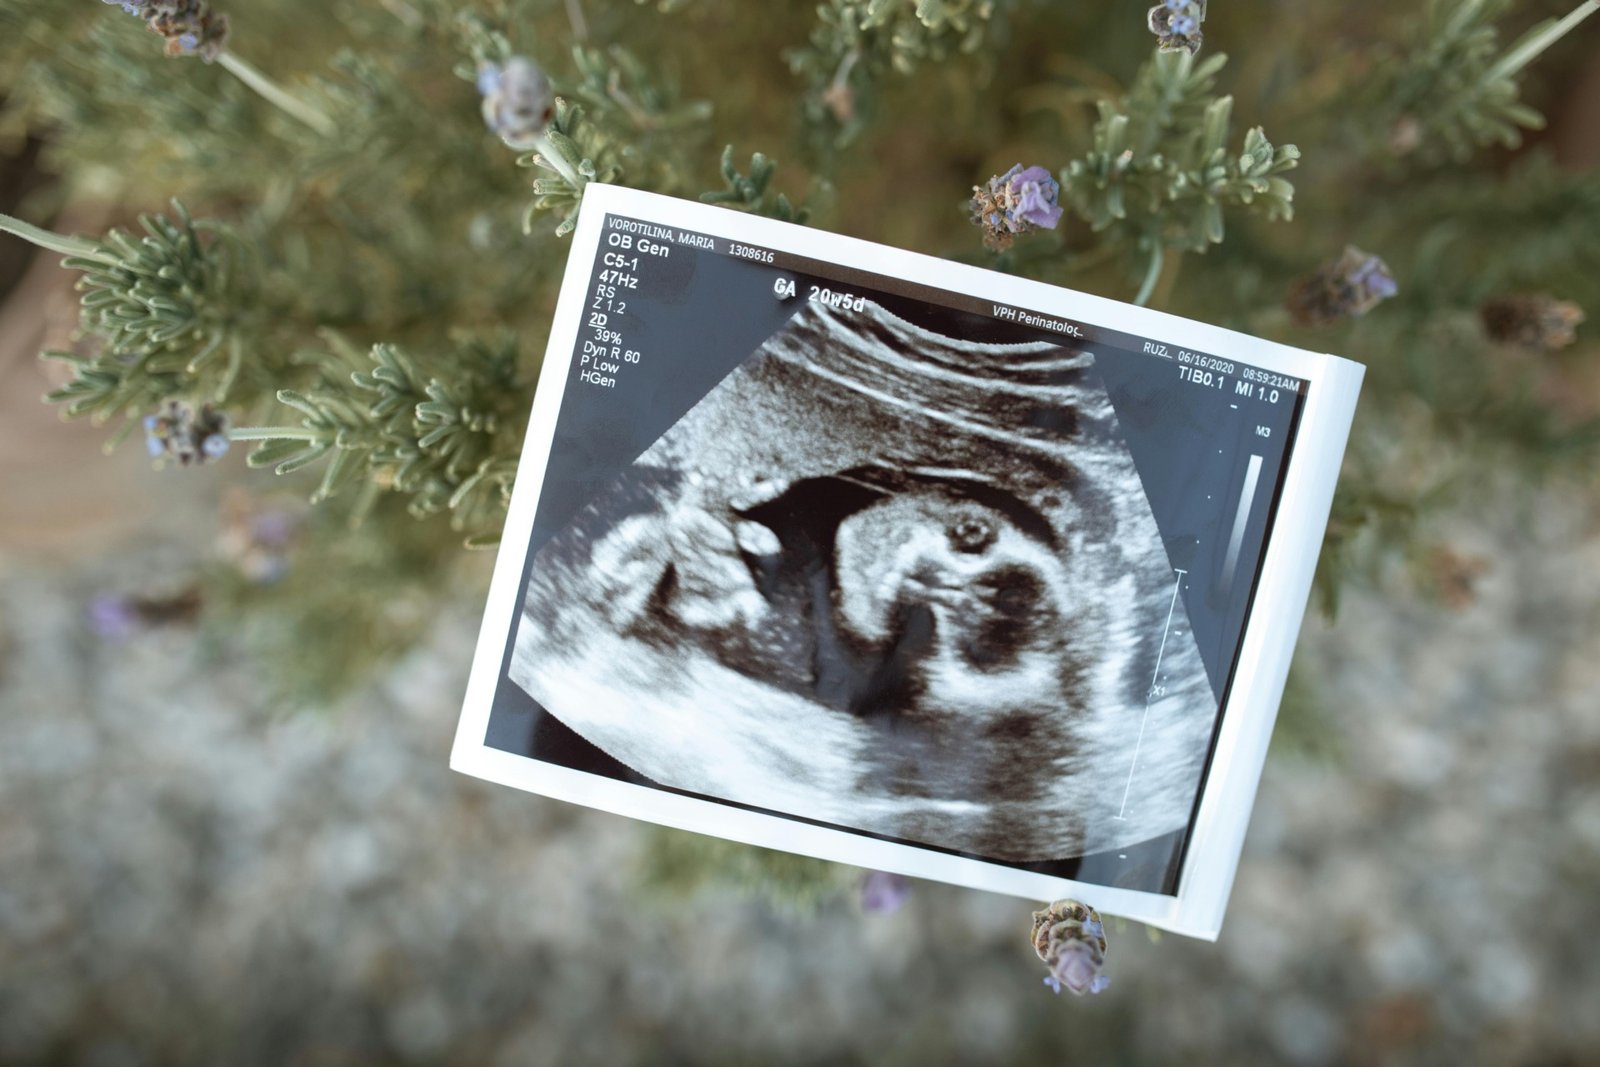

Foto de un feto dentro del útero menudospeques.net/embarazo